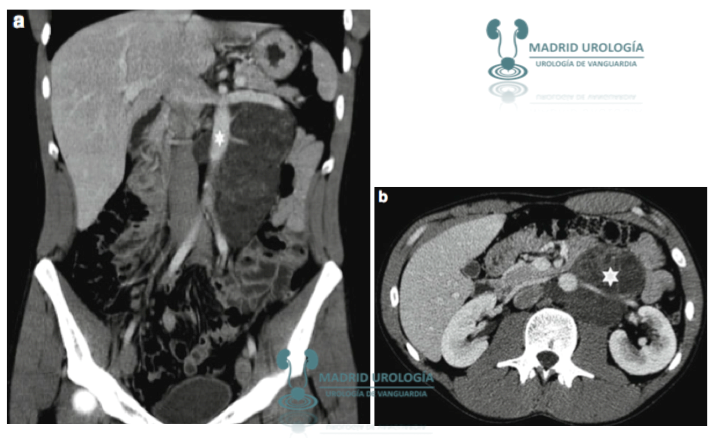

TOMOGRAFIA AXIAL COMPUTARIZADA

El TAC es el estudio estándar para la valoración de vísceras, nódulos retroperitoneales y mediastínicos.

TAC ABD PEL

§ Mandatorio en todos los tipos de TCG.

§ Sensibilidad y VPN se incrementa con cortes de 3 mm.

§ Sensibilidad 70 – 80 % en determinar nódulos retroperitoneales.

§ En estadios I y II la tasa de infra estadiaje es de 25 – 30 %.